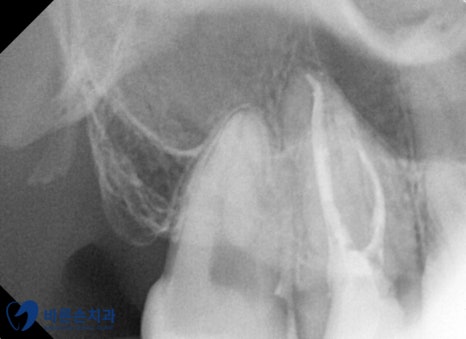

그리고 그 뒤에 있던 사랑니도 같이 발치하였습니다. !

이로써 오른쪽 위는 치료가 끝나셨고,

마취 후 왼쪽 위 아래 사랑니 발치를 하였습니다.

남은 뿌리 없이 깨끗하게 발치 하였고,

다음 날에 소독하러 내원하기로 하셨습니다.^^